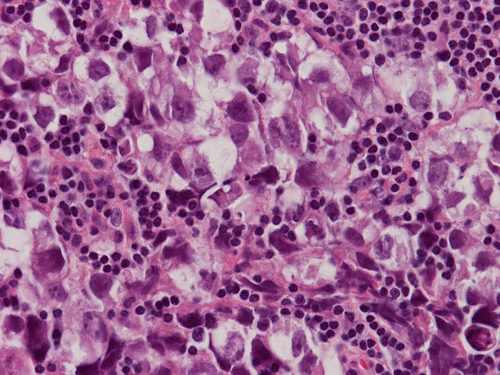

Pathology of the Case: The sample submitted for frozen section has a papillary structure which can be identified as the choroid plexus (Panel C). The center of the choroid plexus is expanded by some large cells accompanied by some smaller cells presumably lymphocytes (Panel D and E). On hematoxylin and eosin stain of the permanent sections, the tumor is composed of clusters of large cells in a background of lymphocytes. On higher magnification, the large cells have enlarged nuclei with prominent nucleoli. No trophoblasts or nor seminomatous component are identified. Immunohistochemistry demonstrated strong positive reactivity for placental alkaline phosphatase (PLAP) (Panel I) and CD117 (c-kit) in the large atypical cells (Panel J). The lymphocytes in the background are strongly immunoreactive for leukocyte common antigen (LCA) (Panel K) but negative for PLAP and CD117.

The discussion here will be limited predominantly to germinoma. Histologically, germinoma has very characteristic features heralded by large, atypical germinoma cells in a background of benign lymphocytes. The germinoma cells are usually huge, with a moderated amount of cytoplasm, and with prominent nucleoli. These cells, even though large, are rarely bizarre. The proportion of germinoma cells with lymphocytes can be highly variable. While most cases show a good mix of both component, the small biopsies yielded by endoscopic biopsy can sample in areas that are lymphocyte predominant or germinoma cell predominant areas which lead to diagnostic pitfalls. It should also be reminded that germinoma has a strong tendency to undergo granulomatous changes. Such granulomatous changes may completely efface the usually big cell-small lymphocyte classic pattern. These biopsies, however, would histologically suggest infection but the clinical history usually would not. Knowing the clinical history is often helpful. Trophoblastic cells could be seen and their presence may indicate a worse prognosis for germinomas. Non-seminomatous component such as embryonal cell carcinoma, yolk sac tumor (endodermal sinus tumor), and choriocarcinoma should also be identified if present.